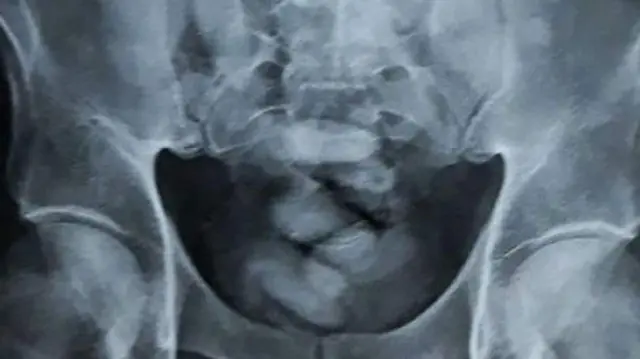

Carallaadhaan ykn X-ray maashinii jedhamuun yommuu ilaalamu garaa isaa keessa meeshaalee baay'een kokeenii baatan akka jiran bira gahamuu aanga'oonni Taayilaandi himaniiru.